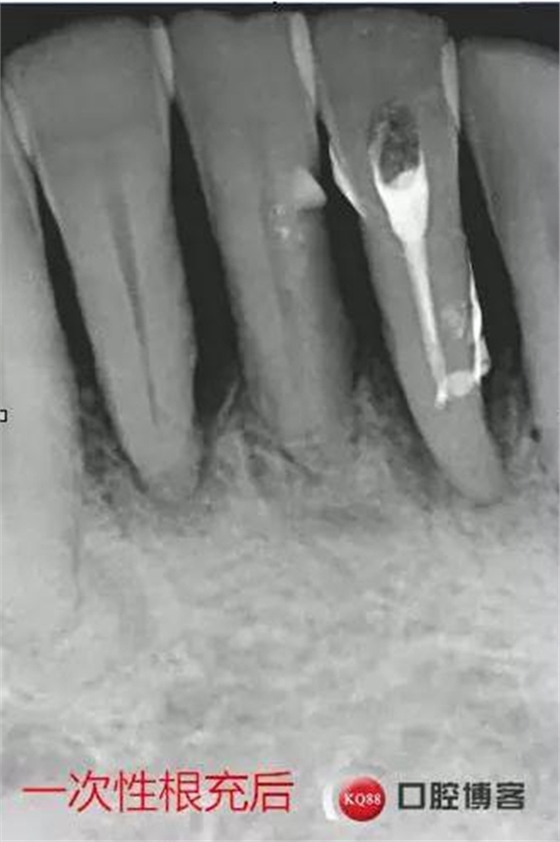

處理:上橡皮障,31開(kāi)髓,測(cè)工作長(zhǎng)度17mm,含氯沖洗液沖洗,機(jī)擴(kuò)至04錐度30#,超聲蕩洗,一次性根充。33-43牙齒鄰接處super bond粘結(jié)固位,行松牙固定。調(diào)合。拍根充術(shù)后片,未達(dá)根尖,懷疑遺漏根管,去除根充物后,繼續(xù)探查根管,找到舌側(cè)根管,測(cè)長(zhǎng)度20mm,時(shí)間原因,未行擴(kuò)根,氫氧化鈣暫封。

圖省事,沒(méi)有拍術(shù)中試尖片,導(dǎo)致術(shù)后重新去除根充物,再次探查,耽誤時(shí)間。

想當(dāng)然的認(rèn)為31單管,忽略了尚有5-10%概率的雙根管情況。

事后再次查看術(shù)前片,可以看到兩個(gè)根管影像,忽略了。